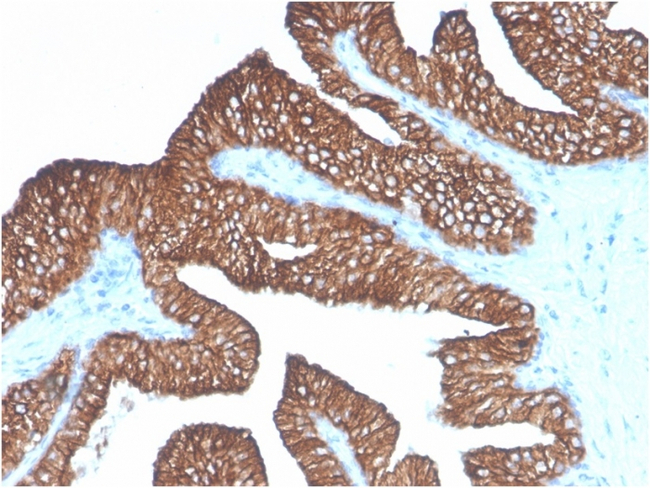

Ep-CAM/CD326 (Extracellular Domain) (Epithelial Marker) Monoclonal Antibody (Ber-EP4)

Ep-CAM (epithelial adhesion molecule, epithelial specific antigen, ESA) is a transmembrane glycoprotein expressed in the epithelium with a molecular weight of approximately 40 kDa, which functions as an epithelial cell adhesion molecule. Ep-CAM functions as a homotypic calcium-independent cell adhesion molecule, and has a direct impact on cell cycle, proliferation and metabolism of epithelial cells and fibroblasts due to its ability to rapidly induce the proto-oncogene c-myc and the cell cycle regulating genes cyclin A and E. Ep-CAM mediates Ca2+-independent homotypic interactions. Formation of Ep-CAM-mediated adhesions have a negative regulatory effect on adhesions mediated by classic cadherins, which may have strong effects on the differentiation and growth of epithelial cells. Ep-CAM overexpression was suggested to be associated with enhanced epithelial proliferation. Ep-CAM is highly expressed in human carcinomas, and is a marker for tumors of epithelial lineage. Ep-CAM is expressed on baso-lateral cell surface in most simple epithelia and many carcinoma types. Also, Ep-CAM reportedly distinguishes adenocarcinomas from pleural mesotheliomas.